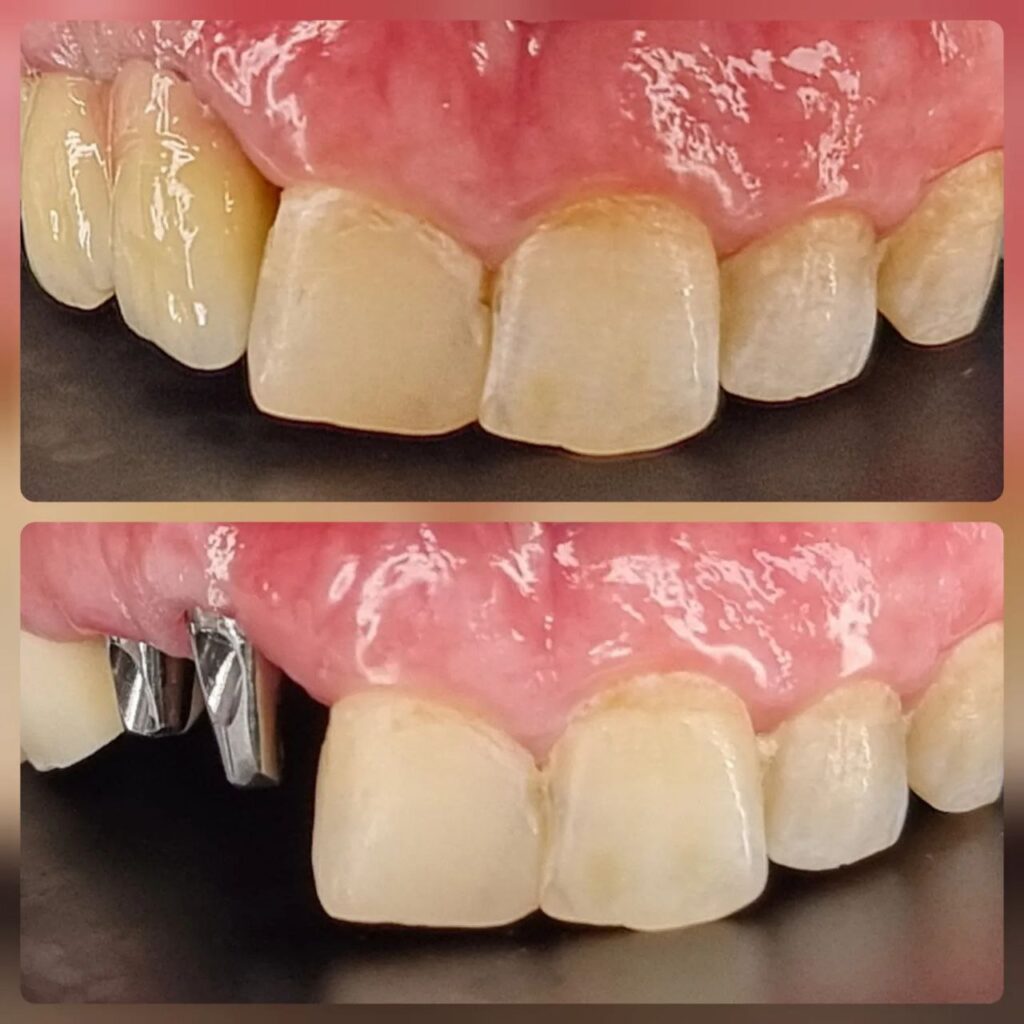

کاشت ایمپلنت دندان

اطمینان حاصل کردن از اینکه دندانهایتان به نحوی زیبا و طبیعی جایگزین شدهاند، از اهمیت بسیاری برخوردار است. ایمپلنت دندان به عنوان یک روش درمانی دائمی در دندانپزشکی شناخته میشود که حاصل آن، یک دندان زیبا و طبیعی در دهان شما خواهد بود.

هرچند که این روش درمانی هزینهی بیشتری نسبت به روشهای دیگر دارد، اما ارزش زیبایی که ایجاد میکند، قابل انکار نیست. ایمپلنتها به قدری شبیه به دندانهای طبیعی هستند که به سختی میتوان آنها را از دیگر دندانها تشخیص داد.